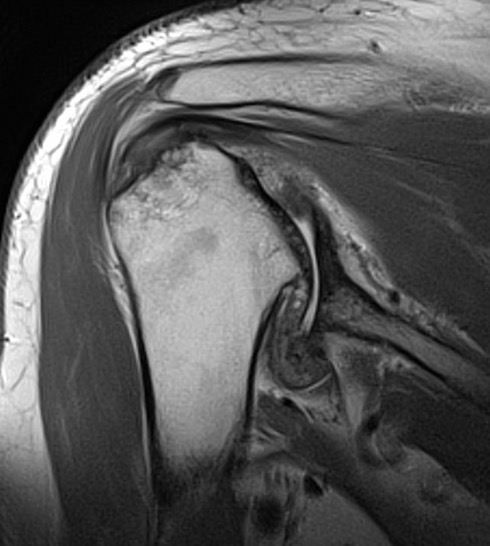

Repaired rotator cuff

MRI demonstrating intact cuff